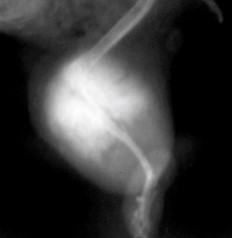

粘液肉腫は線維芽細胞に由来した悪性腫瘍で、ムチンで構成される粘液状のマトリックスを産生します。この腫瘍はどの部位でも発生する可能性があり、ハムスターでは、頬袋や体幹(特に頸周囲)に発生します。腫瘍は大量の粘稠な液体が含まれているため、柔らかいことが特徴です〔Cagnini et al.2011〕。頬袋に発生すると頬袋脱が起こることがあります。